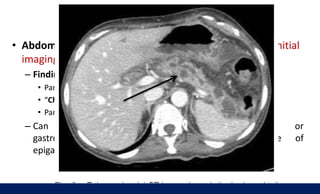

• CT scan: not routinely indicated

– Indications

• At admission: only when the diagnosis is in doubt (e.g., not very highly

elevated pancreatic enzymes, non-specific symptoms)

• > 72 hours of symptom onset: if complications such as

necrotizing pancreatitis or pancreatic abscess (e.g.,

persistent fever and leukocytosis, no clinical improvement or evidence of

organ failure > 72 hours of therapy) are suspected

Diagnosis: Imaging

– Findings:

• Enlargement of

the pancreatic parenchyma with edema; indistinct pancreatic margins with

surrounding fat stranding

• Necrotizing pancreatitis: lack of parenchymal enhancement or presence of air

in the pancreatic tissue

• Pancreatic abscess: circumscribed fluid collection

• Abdominal CT (plain and contrast-enhanced CT): best initial

imaging modality to screen for CP

– Findings

• Pancreatic ductal dilations and calcifications on plain CT

• “Chain of lakes” appearance of the main pancreatic duct

• Pancreatic atrophy

– Can rule out pancreatic carcinoma or

gastrointestinal malignancy as a possible cause of

epigastric pain and weight loss